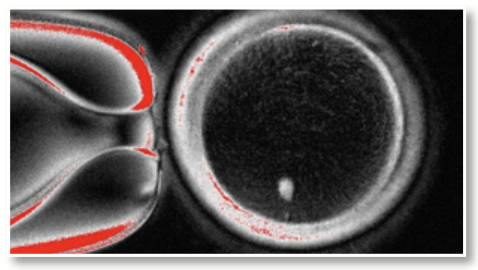

DNA 이중나선을 완전히 자르지 않고 특정 염기 하나만 바꾸는 염기 편집 기술이 개발되며, 3세대 안에서 ‘정밀형 크리스퍼’ 유전자 가위로 진화했다.